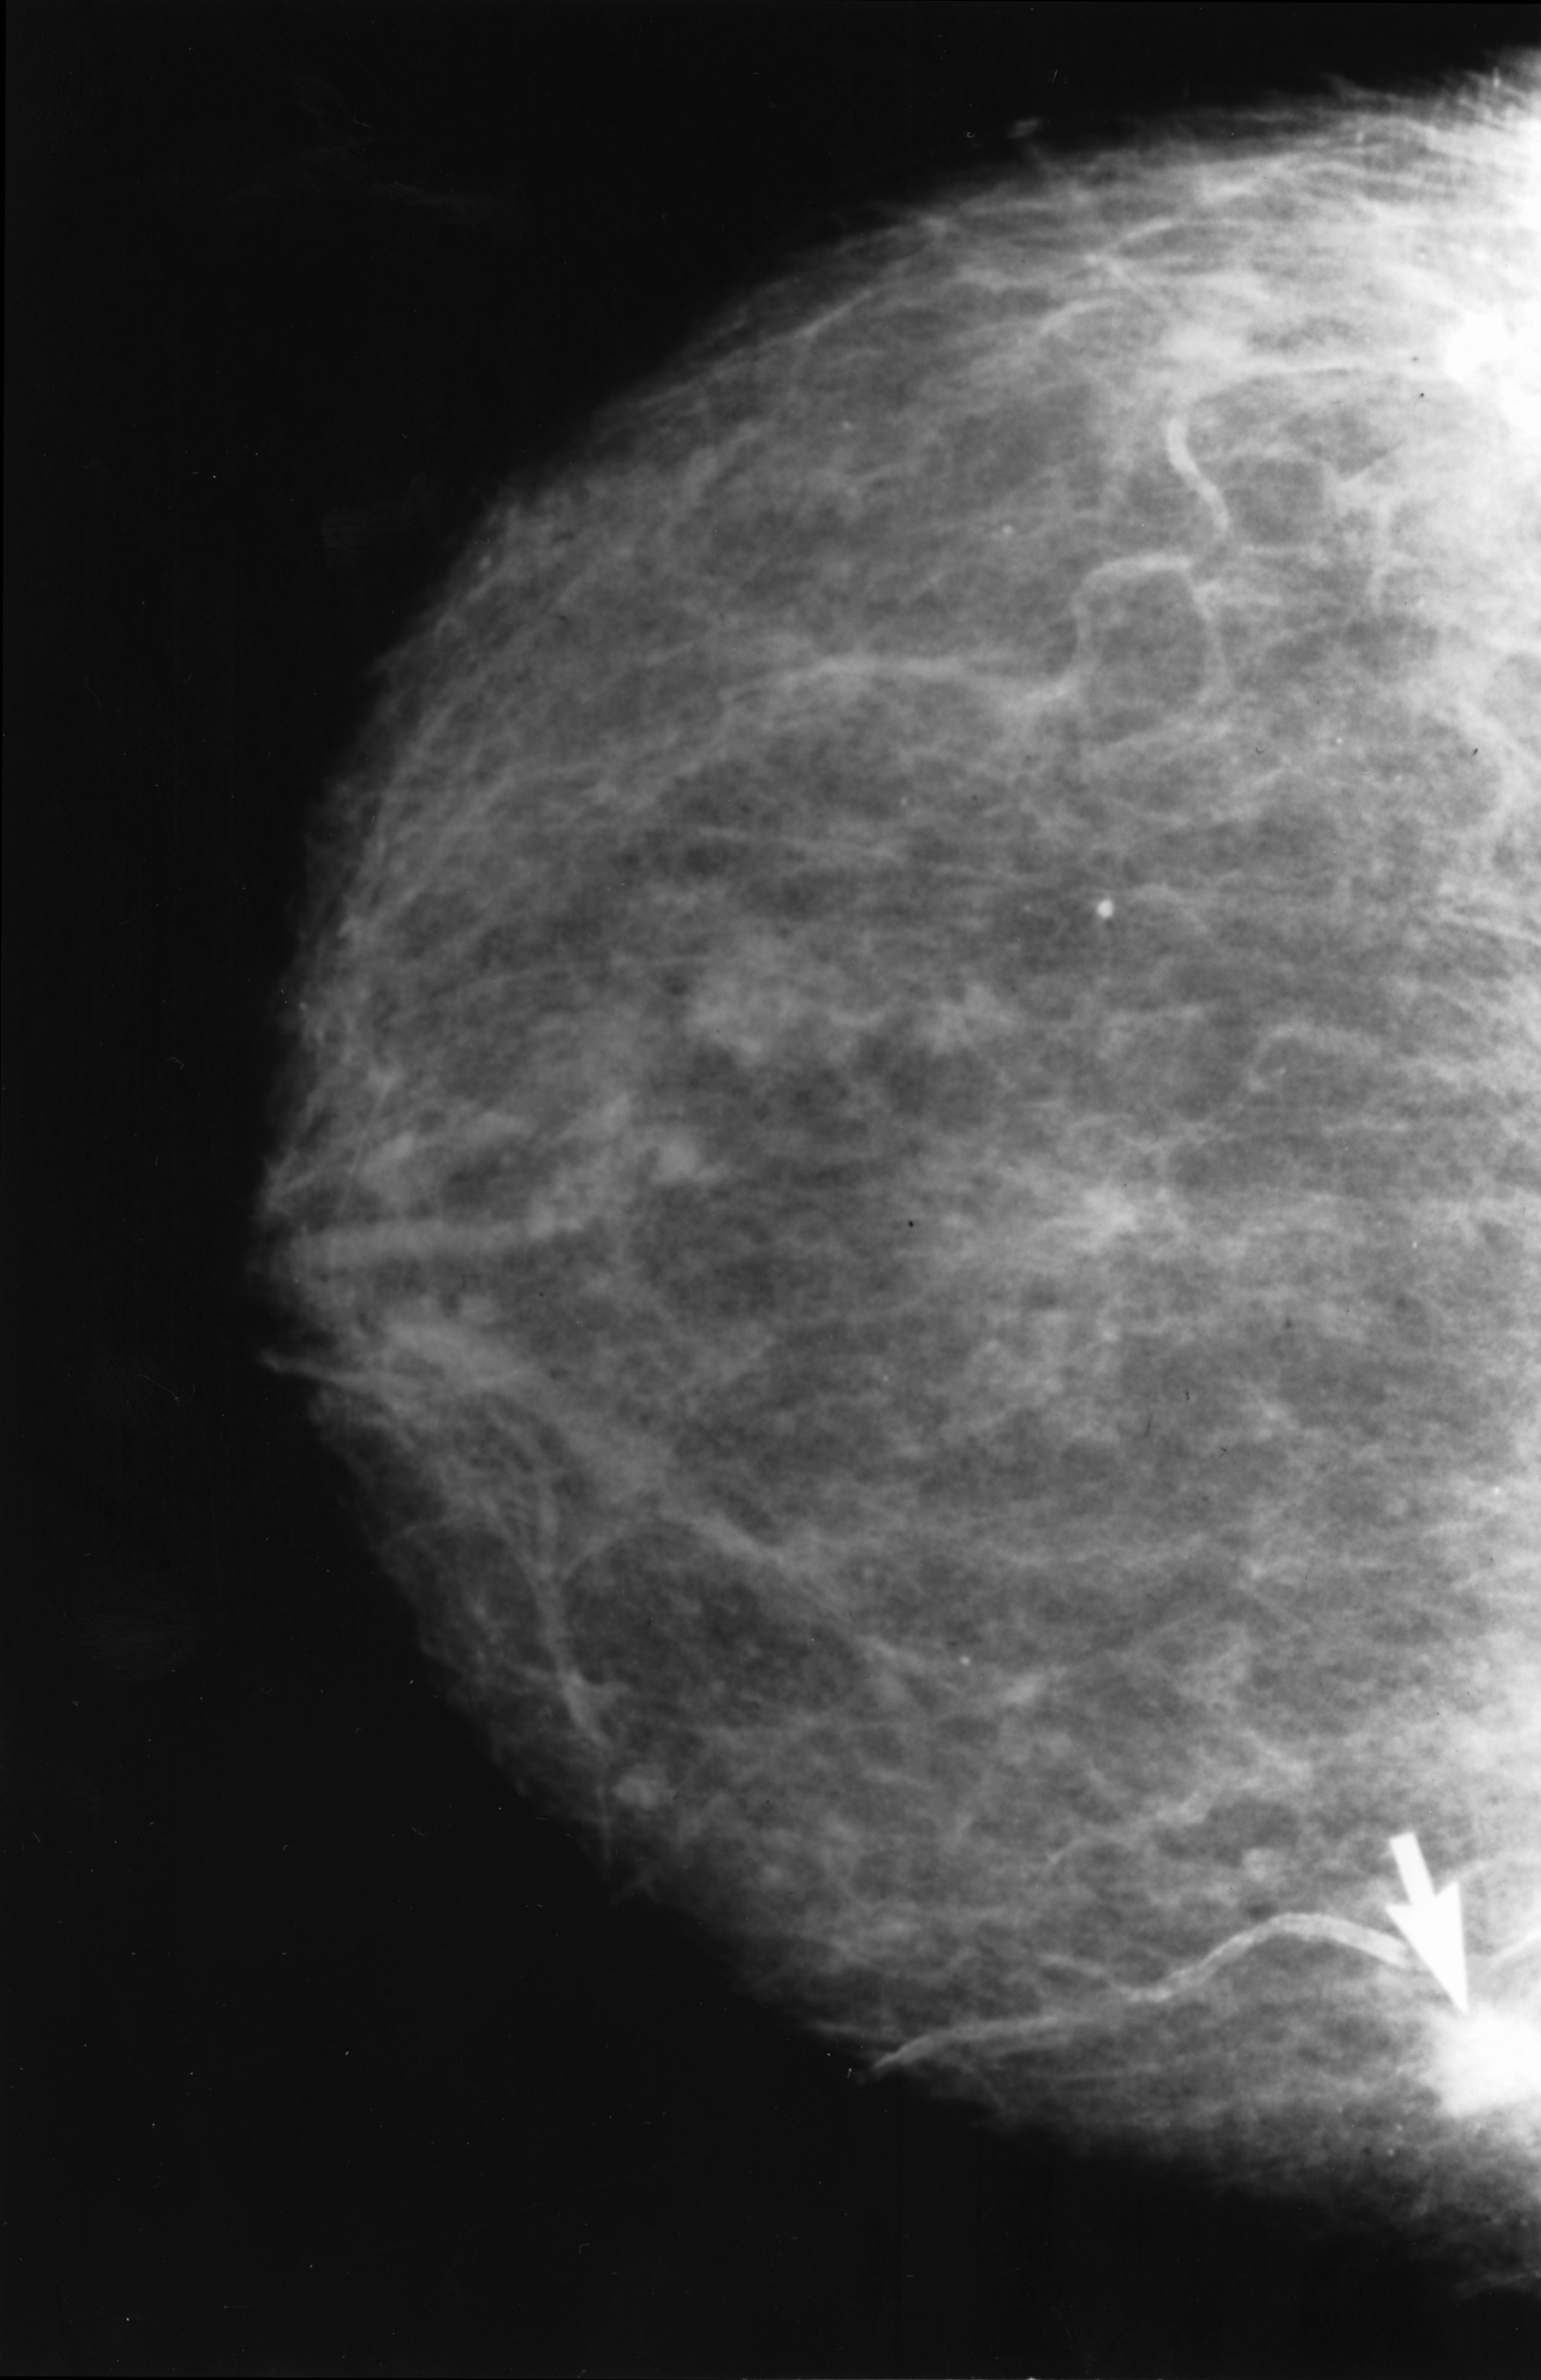

An image of an abnormal mammogram, with an arrow indicating where the tumor is.

Courtesy of Dr. Dwight Kaufman of the National Cancer Institute.

Lumps or masses

There are many types of lumps or masses, like fibroadenomas and cysts, that can be seen on a mammogram. If a mass is at least partly solid, more tests (especially an ultrasound test) may be needed to check if it could be cancerous.